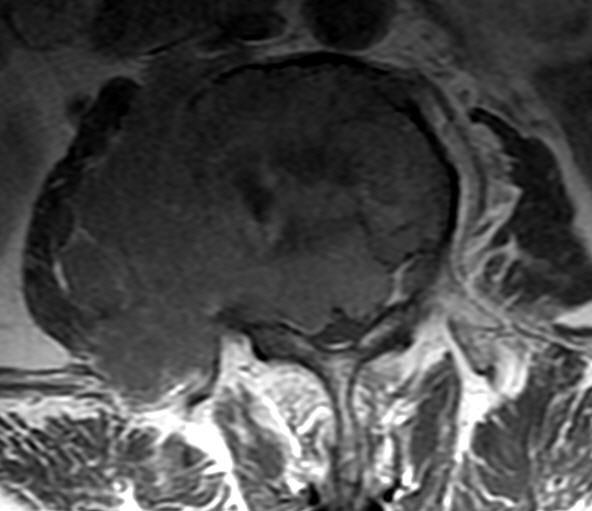

CT

CT可清楚地显示椎管横断面的骨性结构,对侧隐窝狭窄,黄韧带肥厚,椎间小关节病变及神经孔周围极外型椎间盘突出的显示有独特的临床价值,CT可提出比椎管造影更准确的鉴别诊断。CT对蛛网膜下腔观察不如脊髓造影。

MRI

可提供腰椎管的矢状面、冠状面和轴位横断面上的影像。椎管狭窄以T2加权像显示较好,脑脊液为高信号,产生所谓“脊髓造影”的效果,而骨质增生,骨赘、间盘均为低信号,能清晰地显示椎管狭窄,以及对脊髓的压迫情况。但对肥大的黄韧带、骨质增生等的判断则不如较高清晰度CT扫描。

腰椎管狭窄MRI表现。